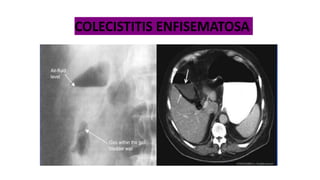

a) COLECISTITIS ACALCULOSA: colecistitis aguda sin colecistolitiasis.

b) COLECISTITIS ENFISEMATOSA: aire aparece en la pared de la

vesícula biliar, debido a la infección por ANAEROBIOS formadores

de gas incluyendo CLOSTRIDIUM PERFRINGENS 50%, E Coli.

Klebsiella, Proteus.

Mortalidad 20%

a) A menudo se ve en los diabéticos.

COLECISTITIS ENFISEMATOSA